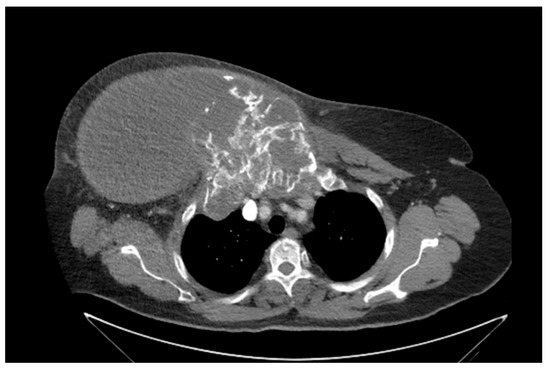

She returned to Bochum in June 2018 with the following symptoms: on the right ventral chest wall, she had a large tumor with a perforation in the pericardium of approximately 15 × 20 cm, an abdominal inguinal tumor on the right, and an ulcerating tumor on the lower left side of the abdomen. A computed tomography of the thorax and abdomen was performed in 09/2018 (Figure 2 and Figure 3) and a magnetic resonance imaging of the thorax was performed in 06/2018 (Figure 4 and Figure 5).

Figure 2.

Computed tomography of thorax and abdomen (CT Thx/Abd) in 2018. In this study, we detected a large tumor on the right anterior thorax with calcifications and invasion in the mediastinum.

Figure 3.

Computed tomography of the thorax and abdomen (CT Thx/Abd) in 2018. There is a large, partially calcified soft tissue structure of the right breast with central hypodensity and possibly mucinous parts. The image shows infiltration of the thoracic wall and transfer to the mediastinum, with destruction of the corpus and manubrium sterni and infiltration of the musculus pecotralis major and the musculus serratus anterior on the right. Additionally, destruction of the adjacent medial clavicle on the right and of the first rib medial on the right was observed. The formation directly infiltrates the mediastinum, with infiltration of the pericardium and direct contact with the aortic arch. The maximum extent of this conglomerate was 25.2 × 14.8 × 10.0 cm (VU 22.7 × 16.6 cm axial; not fully recorded cranially). There was no flow obstruction of the right-side vessels of the upper thoracic aperture.